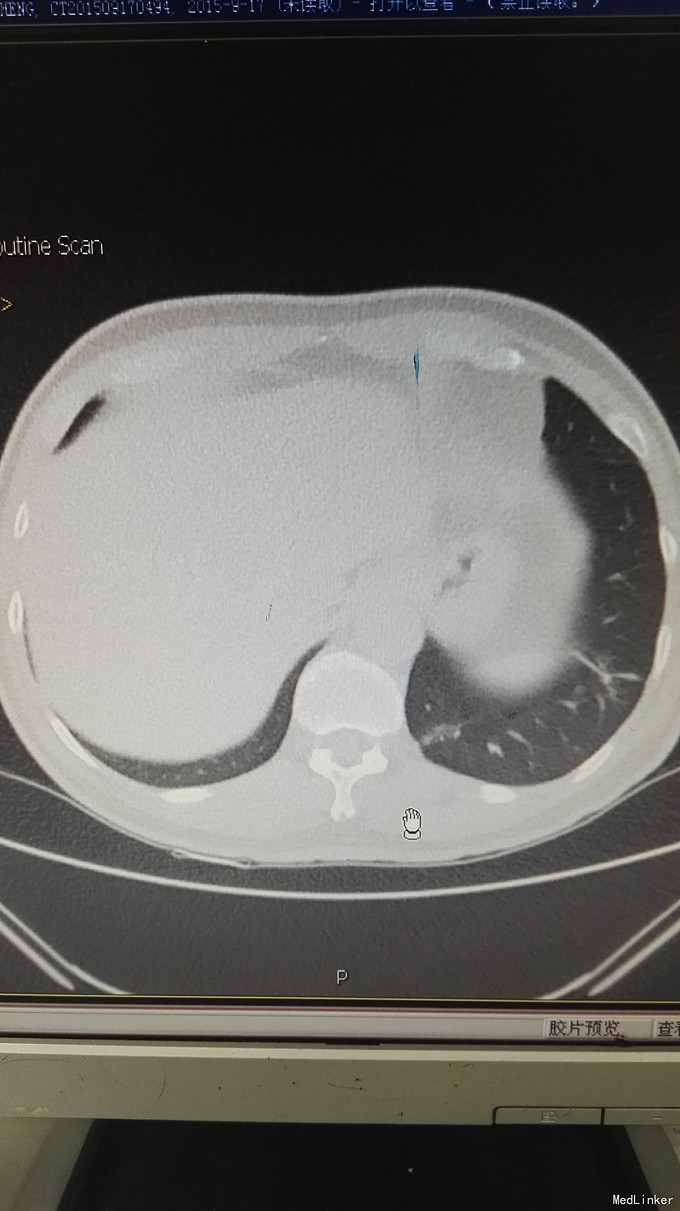

患者男,65岁,退休人员,因体检发现双肺阴影 半月入院。无不适症状。不嗜烟酒,有高血压、糖尿病史。

查体未见异常。 辅助检查:血常规、肿瘤指标、免疫指标、肝肾功能、痰涂片均未见异常。PCT、CRP不高。CT如图:右肺下叶多发斑片状影,左肺上叶蛇段、下叶少许条索状影,考虑双肺慢性炎症。

诊断:双肺阴影查因:肺炎? ; 高血压病 ;2型糖尿病 治疗,目前先进行抗感染及控制血压、血糖处理。